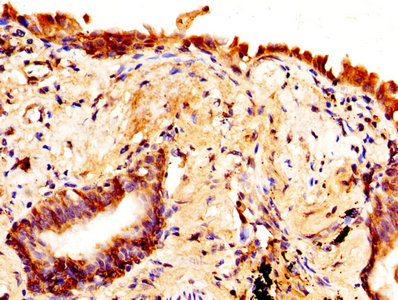

• IHC image of CSB-PA11137A0Rb diluted at 1:370 and staining in paraffin-embedded human lung cancer performed on a Leica BondTM system. After dewaxing and hydration, antigen retrieval was mediated by high pressure in a citrate buffer (pH 6.0). Section was blocked with 10% normal goat serum 30min at RT. Then primary antibody (1% BSA) was incubated at 4°C overnight. The primary is detected by a biotinylated secondary antibody and visualized using an HRP conjugated SP system.